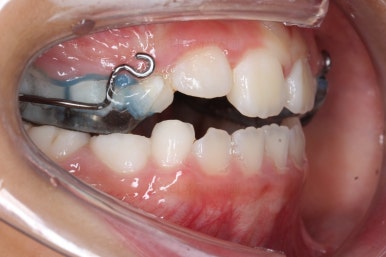

치료를 시작하였습니다.

얼굴 바깥쪽에 마스크를 쓰고, 입 안에 부착된 장치와 고무줄로 연결시켜주면 위턱뼈가 서서히 성장하게 됩니다.

처음 이 장치를 보여드리면 거부감이 굉장히 심합니다. 그래도 하루 12~14시간 끼면 되기 때문에 밤에 집에 있을 때만 착용하면 됩니다.

입안의 장치는 고무줄을 페이스마스크로 걸어주는 매개체 역할도 하고 3차원으로 좁아진 위턱뼈를 양옆으로 넓혀주는 기능도 해요.

이제부터는 위턱뼈를 앞으로 꺼내주고, 양옆으로 넓혀줄 거에요.